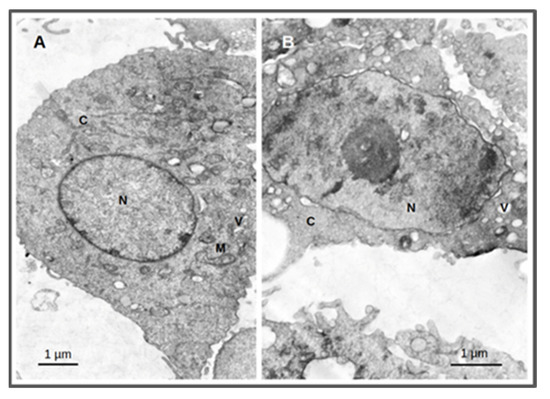

2.3. Cellular Morphological Alterations after Irradiation

4.8.3. Cellular Morphological Alterations by TEM